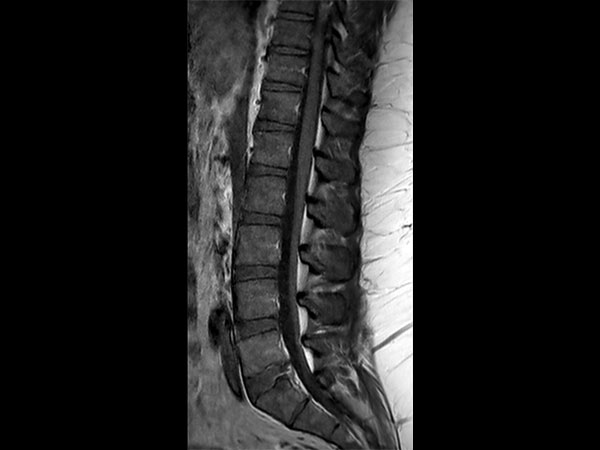

32- year old male patient, 180 kg, with back pain. Was first examined on CT but quality was not sufficient for diagnosis. MRI gave excellent images. Diagnosis: small protrusion of the disc L5/S1, no meningioma.